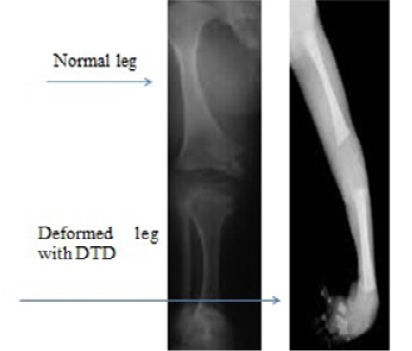

Figure 2

Radiography representation of a normal and DTD leg